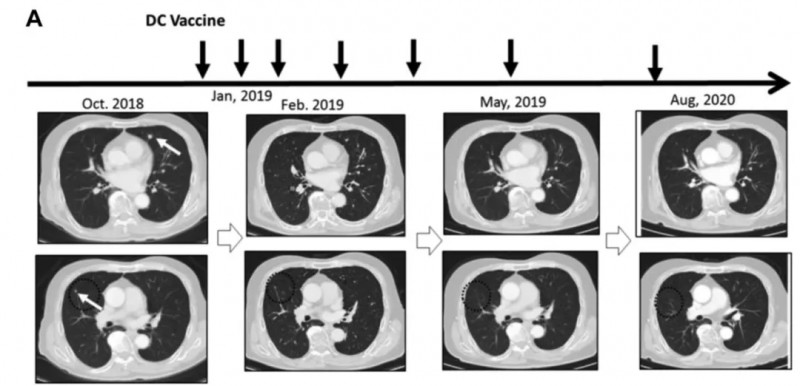

结肠癌肝转移抗复发添重磅方案!DC疫苗让